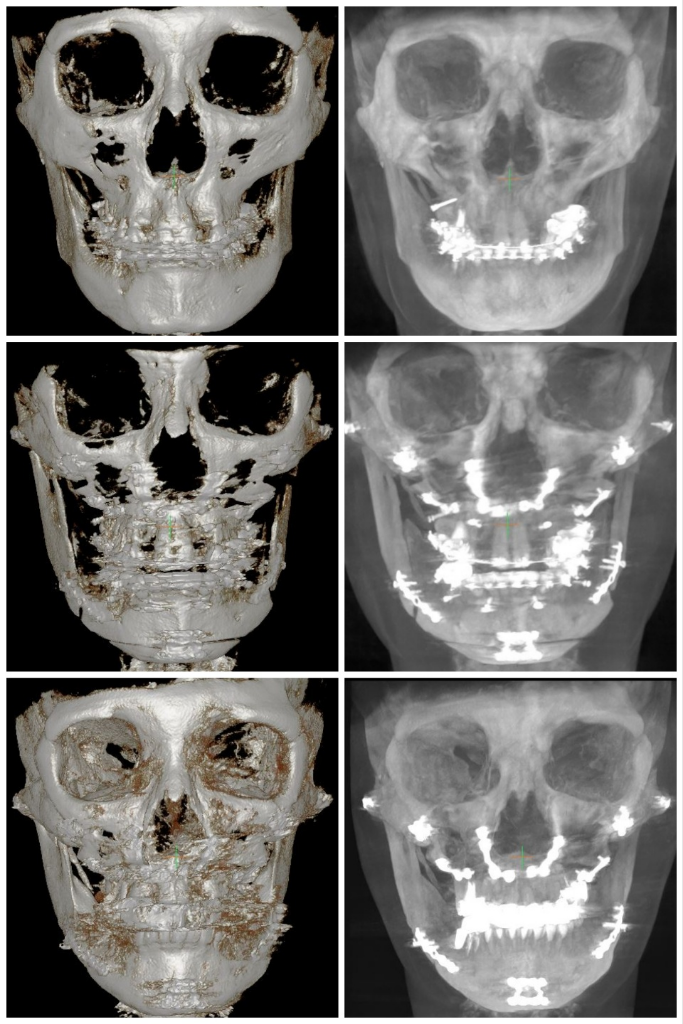

수술 후 제 뼈가 이상한것 같은데 제눈이 이상한건가여?

얼굴형부터 중심선까지 너무 틀어져서요

한쪽이 치아도 그렇고 뒤로 빠져있어요,

근육은 그렇다 쳐도 뼈는 맞춰서 수술해 줘야 하는거 아닌가요?

뼈가 맞춰져 있는데 근육이 비대칭이라서

사진에 저렇게 나온건지ㅠㅠ

현재 상악 임플란트 수술 예정으로 발치후 뼈이식했어요

(핀제거도 다 했어요, 중심이 안맞는것, 교합 좀 봐주세요)

• 4번 째 사진